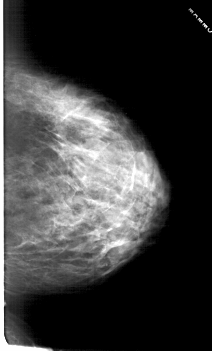

A_1814_1.RIGHT_MLO

RIGHT_MLO LINES 6751 PIXELS_PER_LINE 3781 BITS_PER_PIXEL 12 RESOLUTION 43.5 NON_OVERLAY